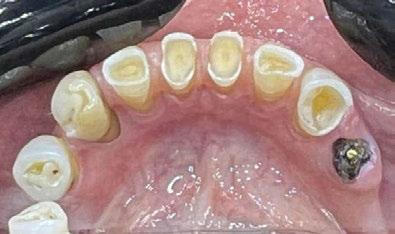

Exploración Intraoral

Presenta un estado oral deficitario. Parcialmente edéntula, con colapso de mordida, migración dental patológica, restauraciones de resina antiguas fisuradas y filtradas, transparencia y exposición de cámara pulpar secundaria a desgastes con pérdida de estructura e integridad de tejido dental importante (Figuras 1 a 4). Portadora a tiempo parcial de prótesis removibles desadaptadas de más de 10 años de antigüedad, refiriendo incapacidad de adaptación a este tipo de prótesis.

Figura 3. Visión intraoral oclusal mandibular. Figura 4. Visión intraoral frontal. Figura 1. Visión intraoral oclusal maxilar. Figura 2. Visión lateral izquierda intraoral. Figura 7. Escaneado intraoral maxilar con Dexis IS3700. Figura 8. Escaneado intraoral mandibular con Dexis IS3700. Figura 5. Visión extraoral lateral sonrisa.